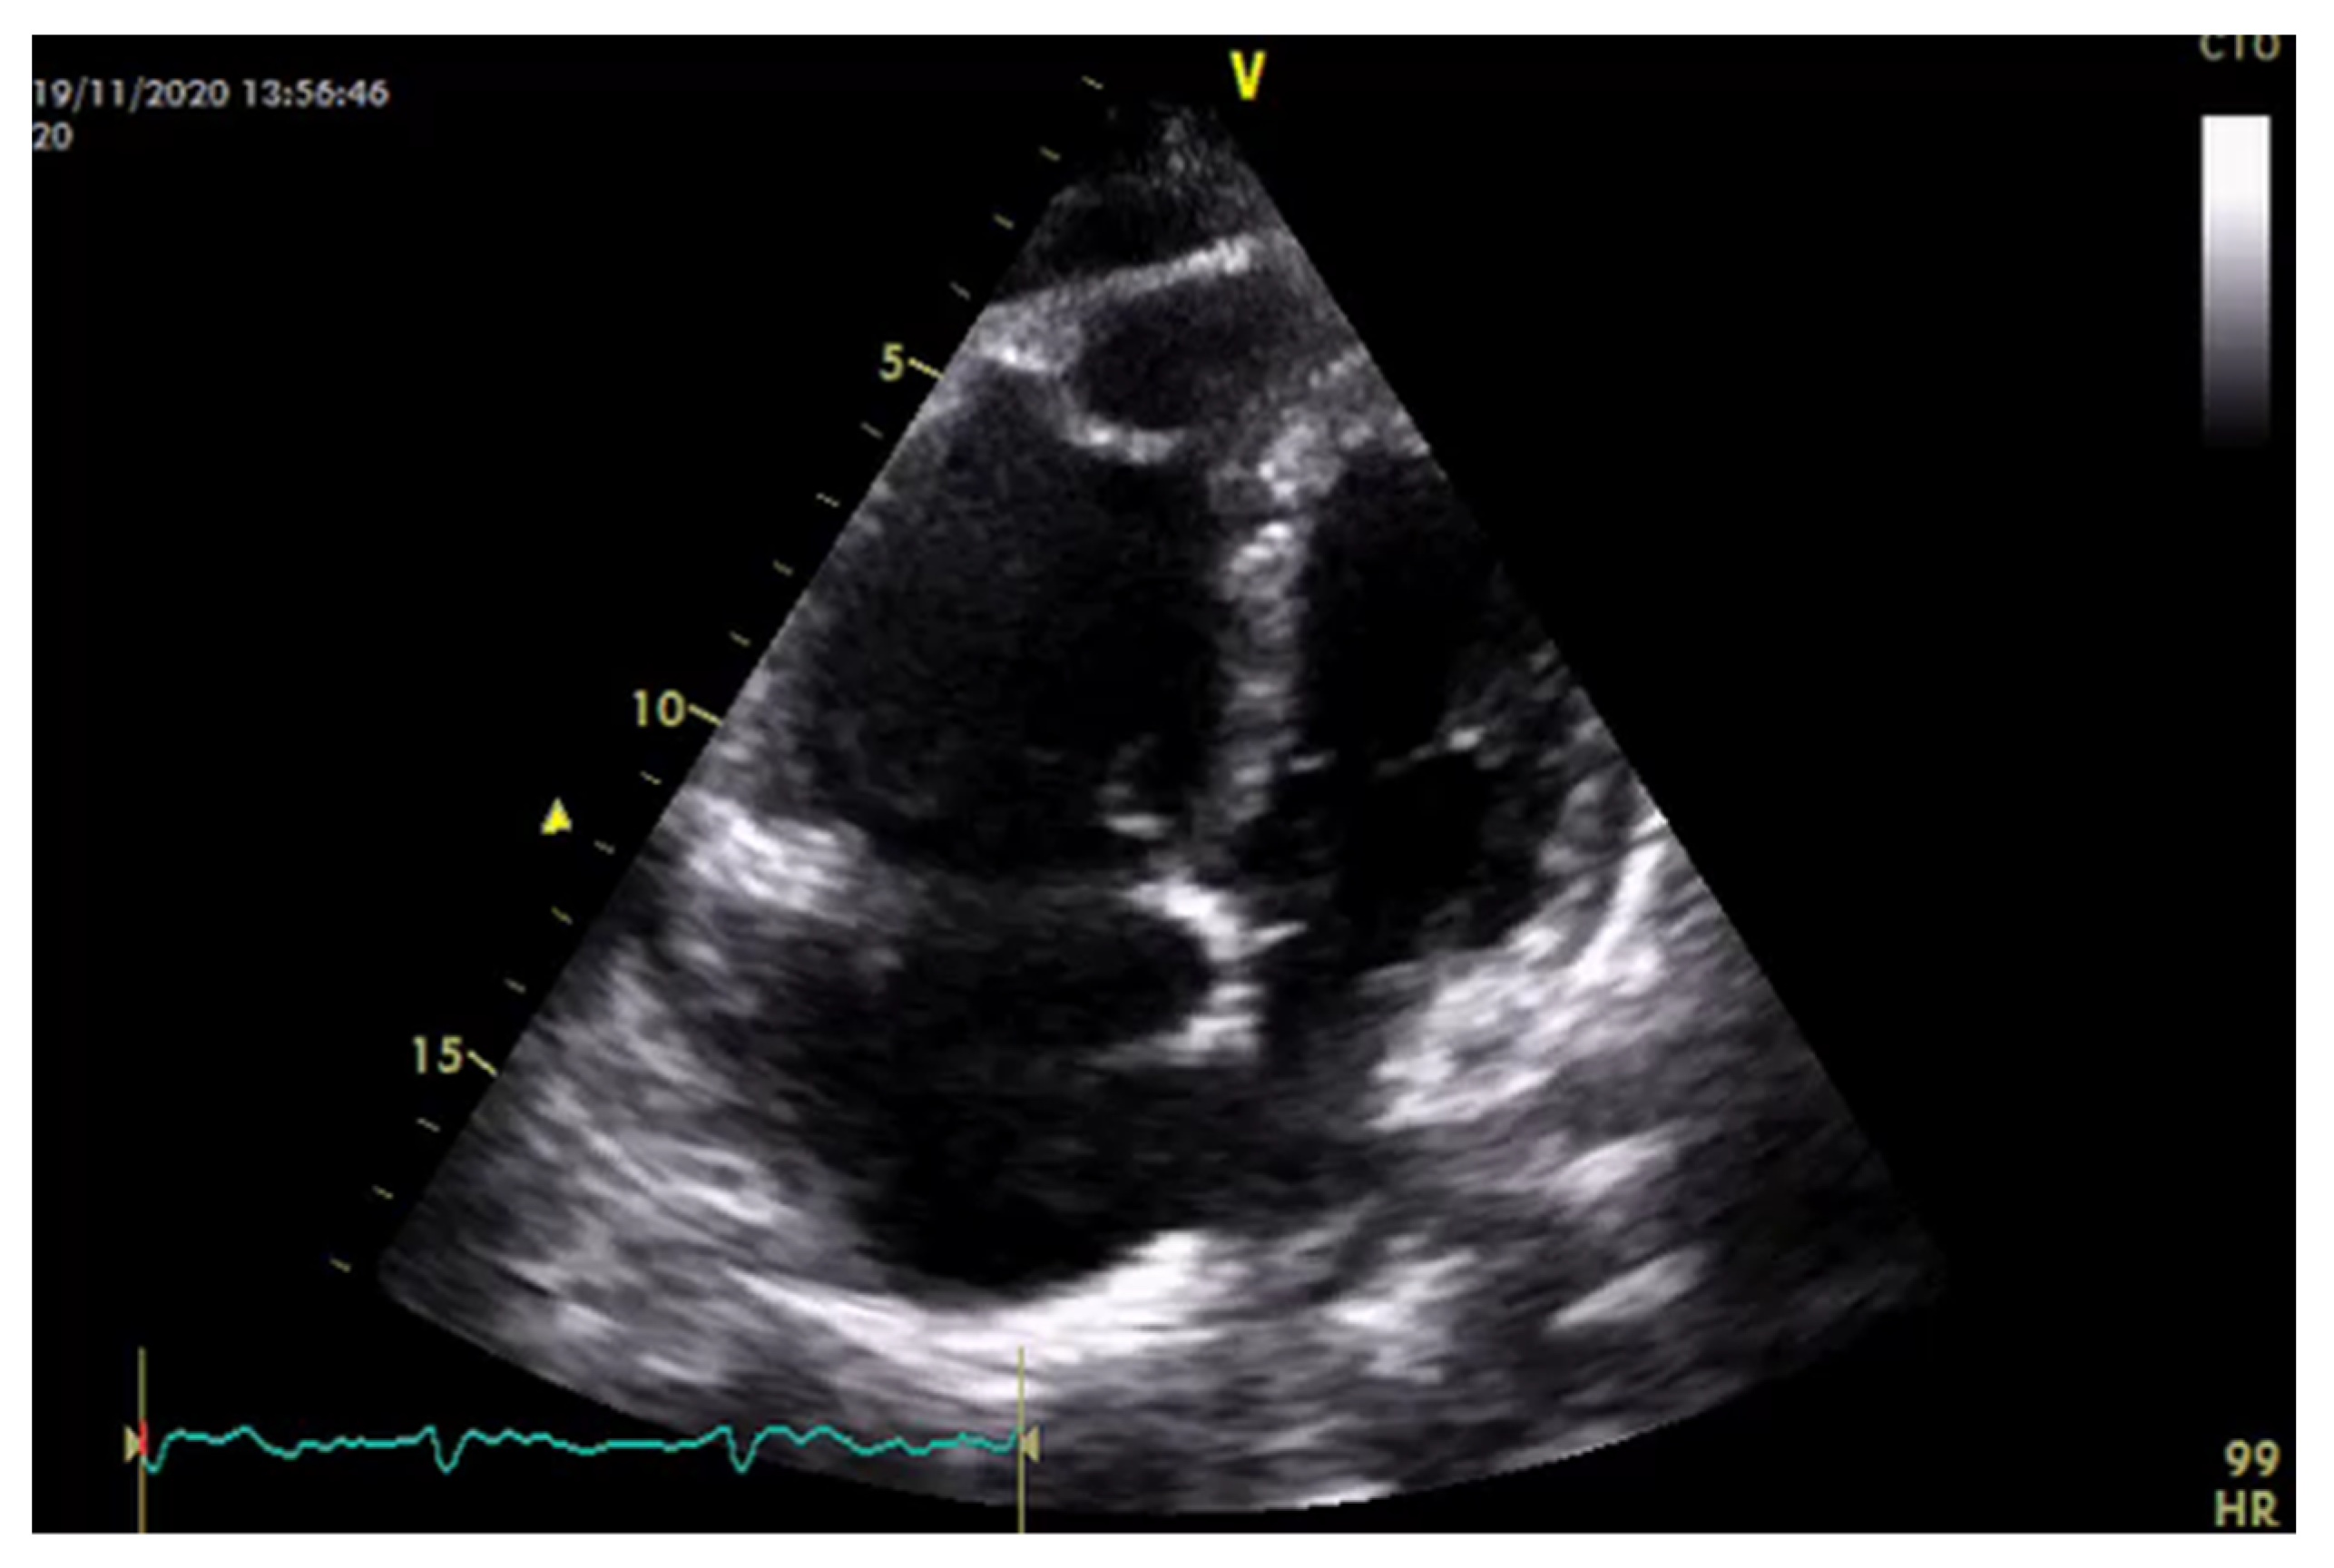

| Perfusion parameters | LVOT VTI and CI | A reliable quantitative parameter that truly reflects circulatory status and global end organ perfusion | LVOT VTI ≥ 18 cm CI ≥ 2.5 L/min/m2 |

| RVOT VTI | Gives information about the right ventricle function and pulmonary vascular resistance | RVOT VTI ≥ 12 cm | |

| RV 2D FAC | Provides an estimate of global RV systolic function | RV FAC ≥ 35% | |

| TAPSE | Represents a measure of RV longitudinal function | TAPSE ≥ 17 mm | |